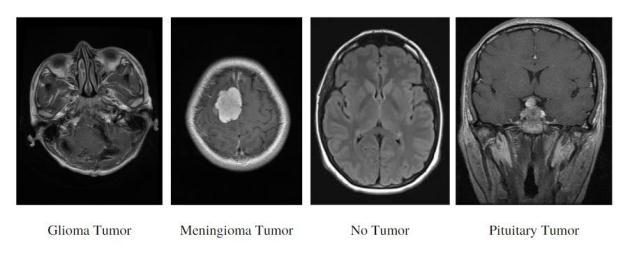

The dataset contains a total of about 5000 MR images divided into three different tumor types (Glioma, Meningioma and Pituitary) and one class of healthy brain depictingNotumor.

SampleMRImagesofallclassesarerepresentedinFig-7:

Fig - 7:SampleInputImages Fig - 8:ProposedMethodologyArchitecture

AfterconvertingimagesintoN-Darrays,thenextstepisto train the model. Before training the model, since this is a classificationproblemandthedataisintheformofimages, CNN and transfer learning methodologies can be used to train the model. In the proposed system five different ideologies are been used i.e. Custom CNN with 6-layered architecture,MobileNETtransferlearning model,VGG- 16 transfer learning model, ResNET-152 transfer learning model and DenseNET-169 transfer learning model. These wereproventobethebestasfarasrobustnessandaccuracy areconcerned.Oncethemodelistrainedandanalyzed,the sametrainedmodelcanbeusedforanynewunseenimages to predict the type of tumor that is present inside it. For testing new unseen images, the same ideology of preprocessingwillbeappliedonitandthenitwillbepassed through these trained models and finally the prediction whethertheMRIcontainsthepituitarytumor,gliomatumor, meningiomatumorornotumorispresent.Currentlyonly thesefourclassesareavailableandinfuturemoreclasses canalsobeintegratedwiththeexistingdatatoextendthe scopeoftheproject.